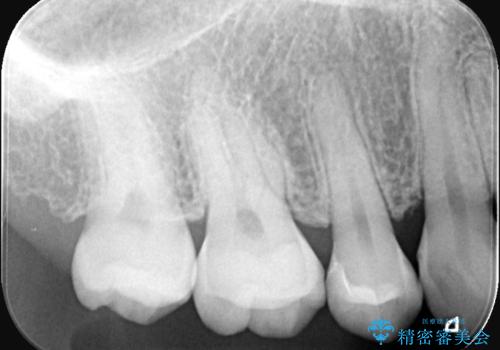

- 右上5番(小臼歯)の咬み合わせの面(咬合面)に小さな穴があることを主訴にご来院されました。視診およびレントゲン検査の結果、表面の穴は小さいものの、内部で虫歯が広がっていることが確認されました。患者様から「目立たないように治したい」というご希望があったため、健全な歯質を極力残しながら、審美性と耐久性に優れた**セラミックインレー(詰め物)**で修復する計画を立案しました。

治療ではまず、小さな穴から内部に広がっていた虫歯を、マイクロスコープ(歯科用顕微鏡)等を用いて精密に除去しました。虫歯を取り除いた後の空洞を整え、歯との適合性を高めるための精密な型取りを行いました。